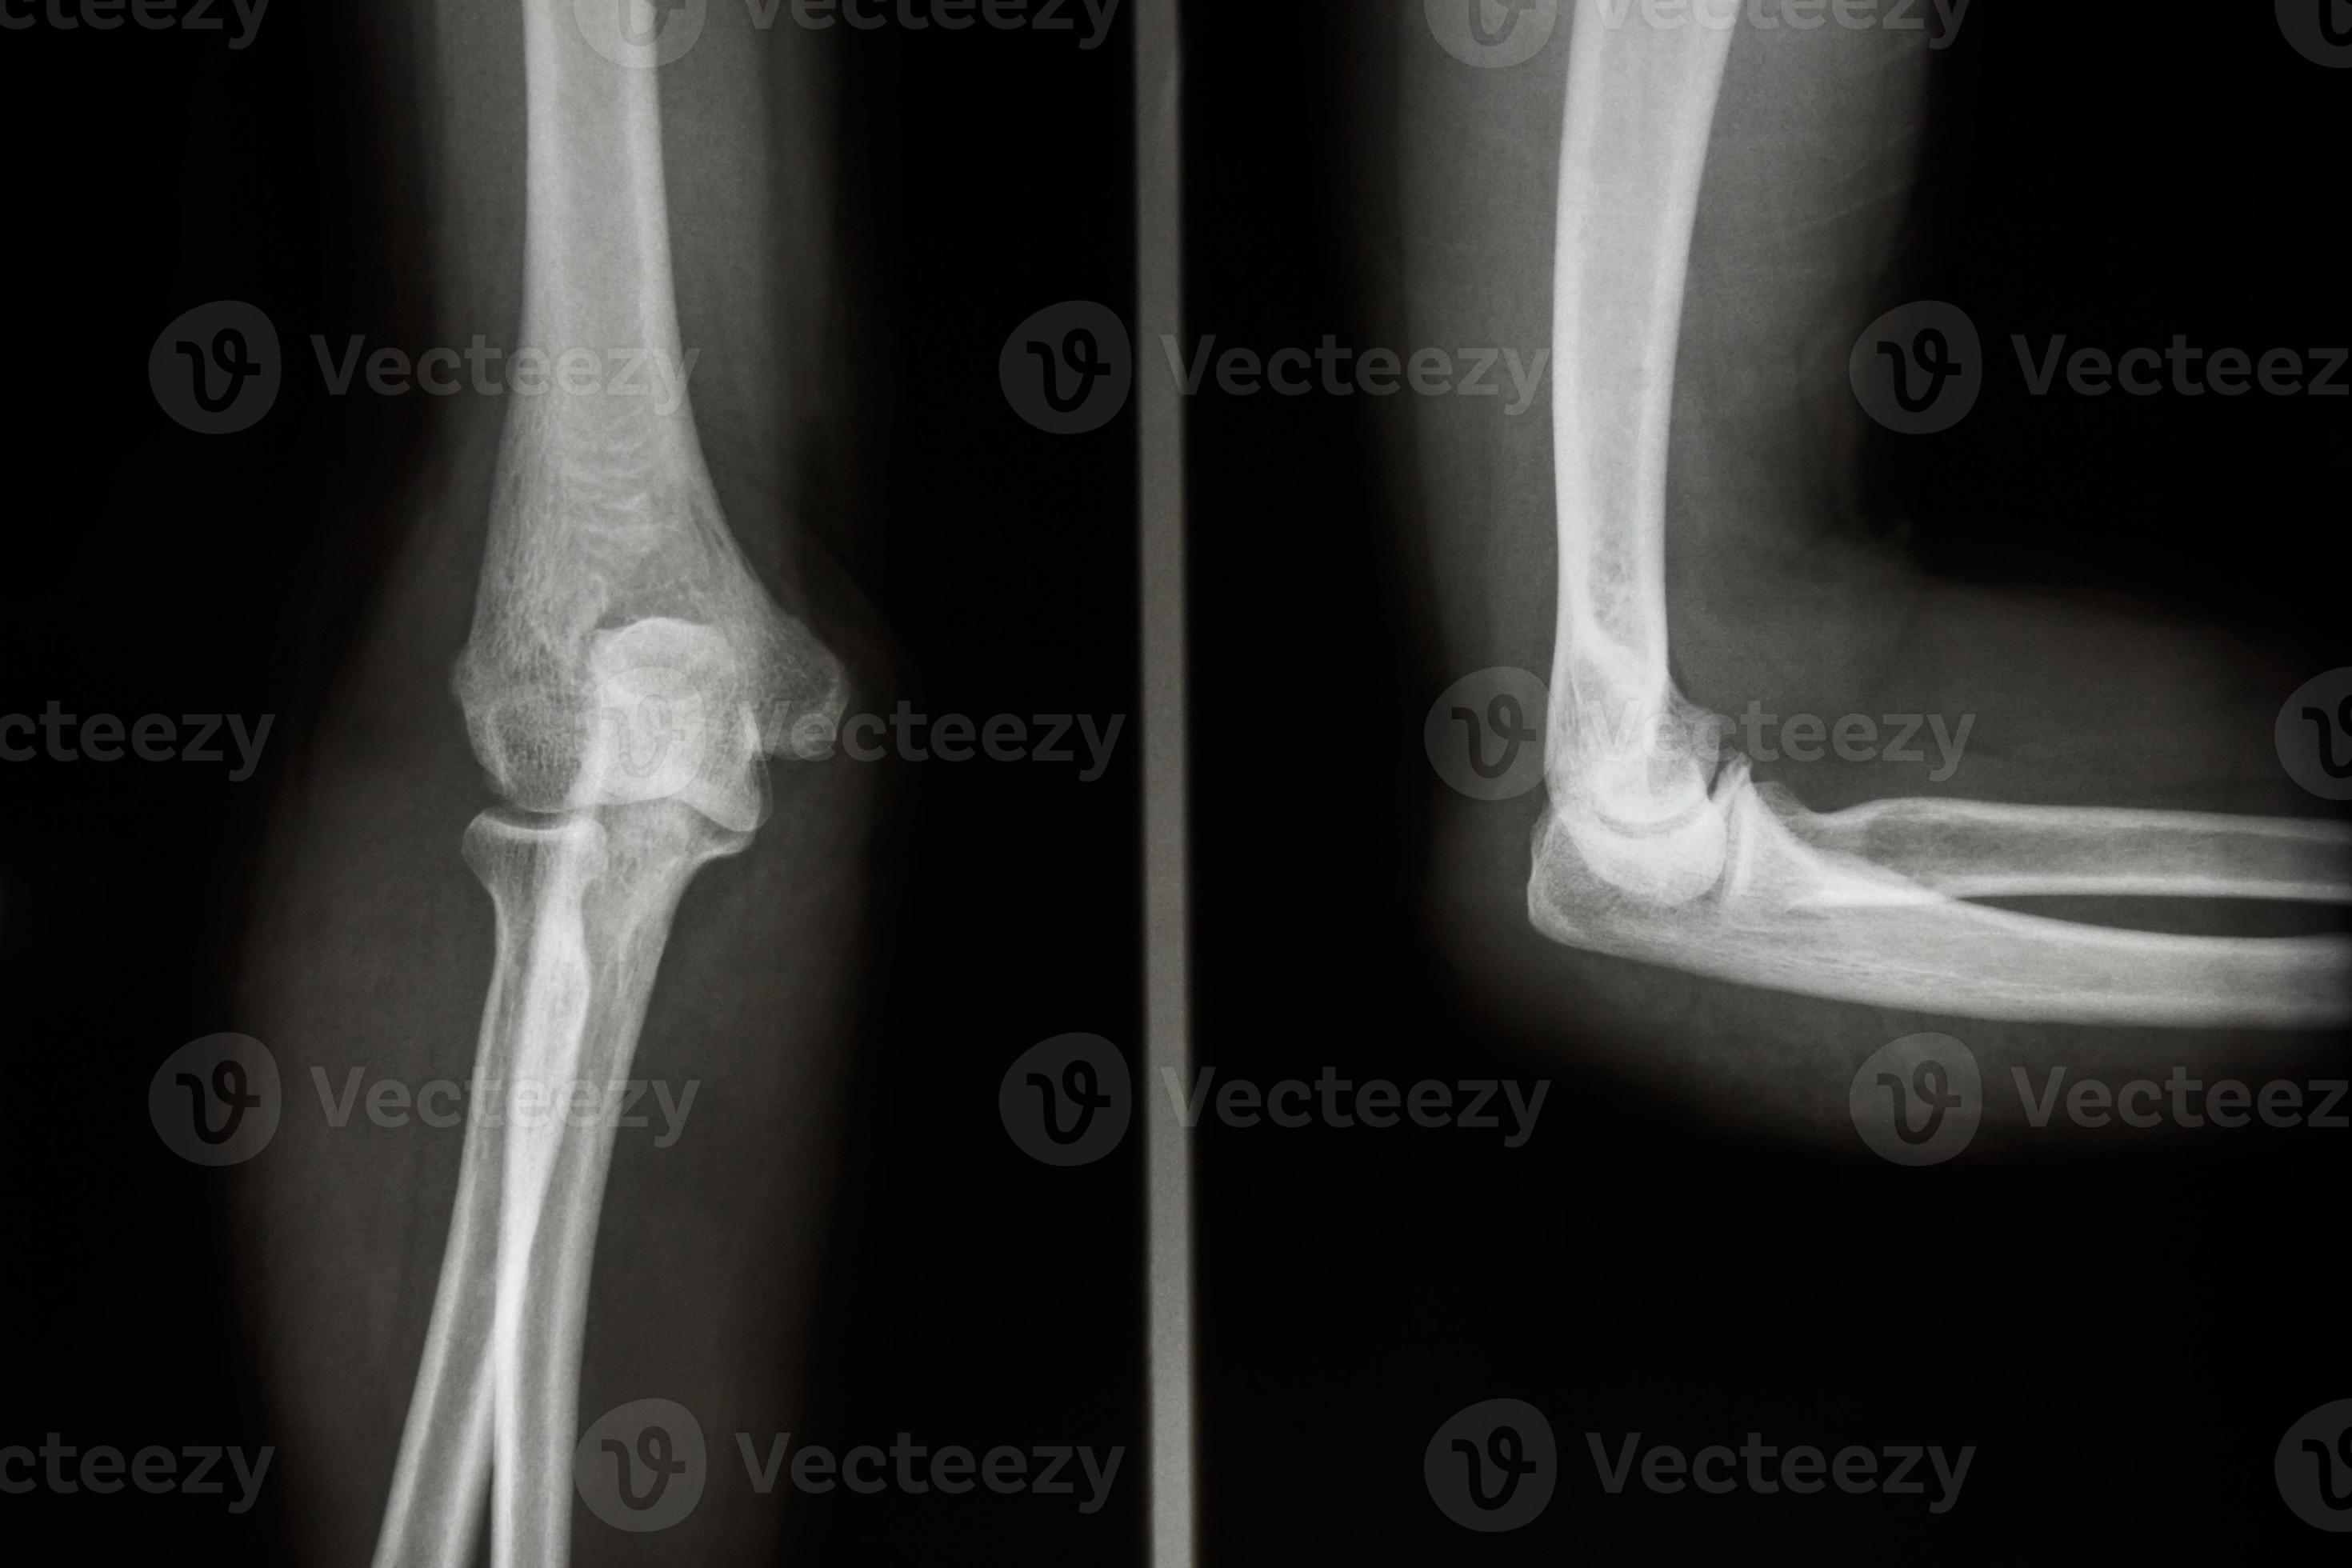

From www.vecteezy.com

film xray elbow AP and Lateral view show normal human s elbow 2493647 What Is Elbow X-Ray If you can see one, this is automatically abnormal and indicates a fracture. This is an abnormal effusion of the joint that indicates a fracture is present (even if you can’t see it!) you should never be able to see a posterior fat pad. Though there have been advances in elbow imaging in the past couple decades, conventional radiography remains. What Is Elbow X-Ray.